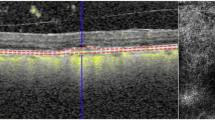

A total of 291 OCTA images in consecutive visit of 45 patients newly diagnosed with type 1 NMV and treated with three loading intravitreal anti–vascular endothelial growth factor injections (IVIs) and a pro-re-nata (PRN) therapy regimen were analysed. Quantitative features of OCTA included the MNV area, MNV length, total number of endpoints (open-ended vessels) and junctions (internal branching) using AngioTool. Two subgroups were divided according to exudation recurrence time from the third IVI (group 1: ≤3 months vs. group 2: >3 months).

The area, length, number of total junctions, and endpoints decreased during three loading IVIs and increased at exudation recurrence (all p < 0.05). In a subgroup analysis of consecutive OCTA images, the number of total endpoints increased at two months prior to exudate recurrence in group 2 (the late recurrence group, p = 0.020). A higher total number of endpoints of MNV at baseline were found to be related with group 1 (early recurrence, p = 0.020 and 0.012 in univariate and multivariate regression analyses).

The MNV with higher open-ended vessels at the lesion periphery at baseline might be expected to show earlier recurrence of exudation after loading IVIs. By observing the number of open-ended vessels in consecutive OCTA images, exudation recurrence could be predicted.